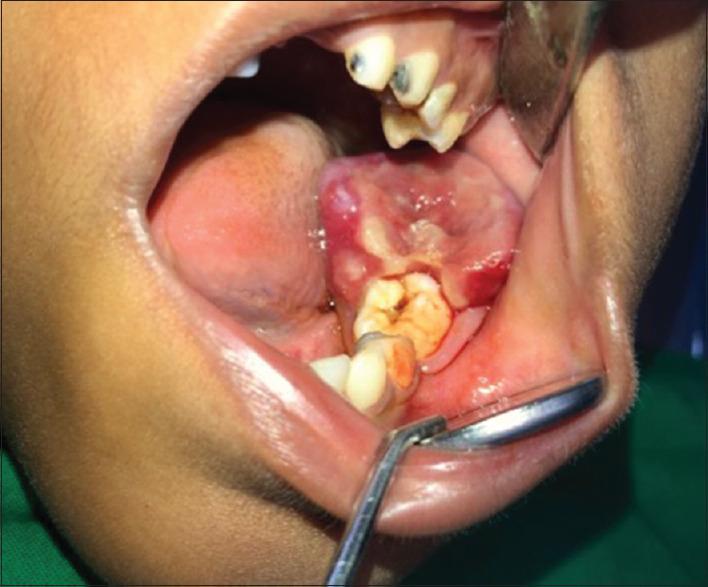

Inflammatory myofibroblastic tumor (IMT) of the oral cavity is an extremely rare finding. The etiology and pathogenesis of IMT is controversial and unclear. The tumor requires complete surgical excision and continuous monitoring of clinical consequences. The present article describes the clinical, histological, operative and immunohistochemical features of a case of IMT in the mandibular retromolar region of an 8-year-old male. Histologically, the lesion shows myofibroblastic spindle cell proliferations with infiltrative margins in an inflammatory background. Immunohistochemically, the myofibroblastic spindle cells in the present case were positive for α-smooth muscle actin and CD68 due to which the diagnosis of IMT was confirmed.

口腔炎性肌纤维母细胞瘤(IMT)极为罕见。IMT的病因和发病机制存在争议且尚不明确。该肿瘤需要完整手术切除并持续监测临床后果。本文描述了一名8岁男性下颌磨牙后区IMT病例的临床、组织学、手术及免疫组化特征。组织学上,病变显示在炎症背景下肌纤维母细胞梭形细胞增生,边界浸润。免疫组化方面,本例中的肌纤维母细胞梭形细胞α-平滑肌肌动蛋白和CD68呈阳性,据此确诊为IMT。